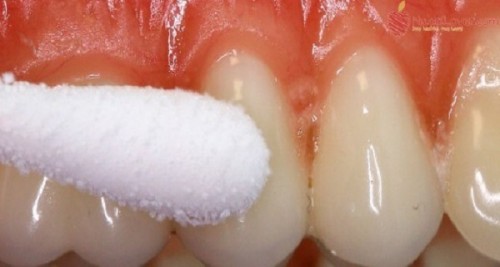

Trajtoni ulcerat e gojës me këto mënyra natyrale